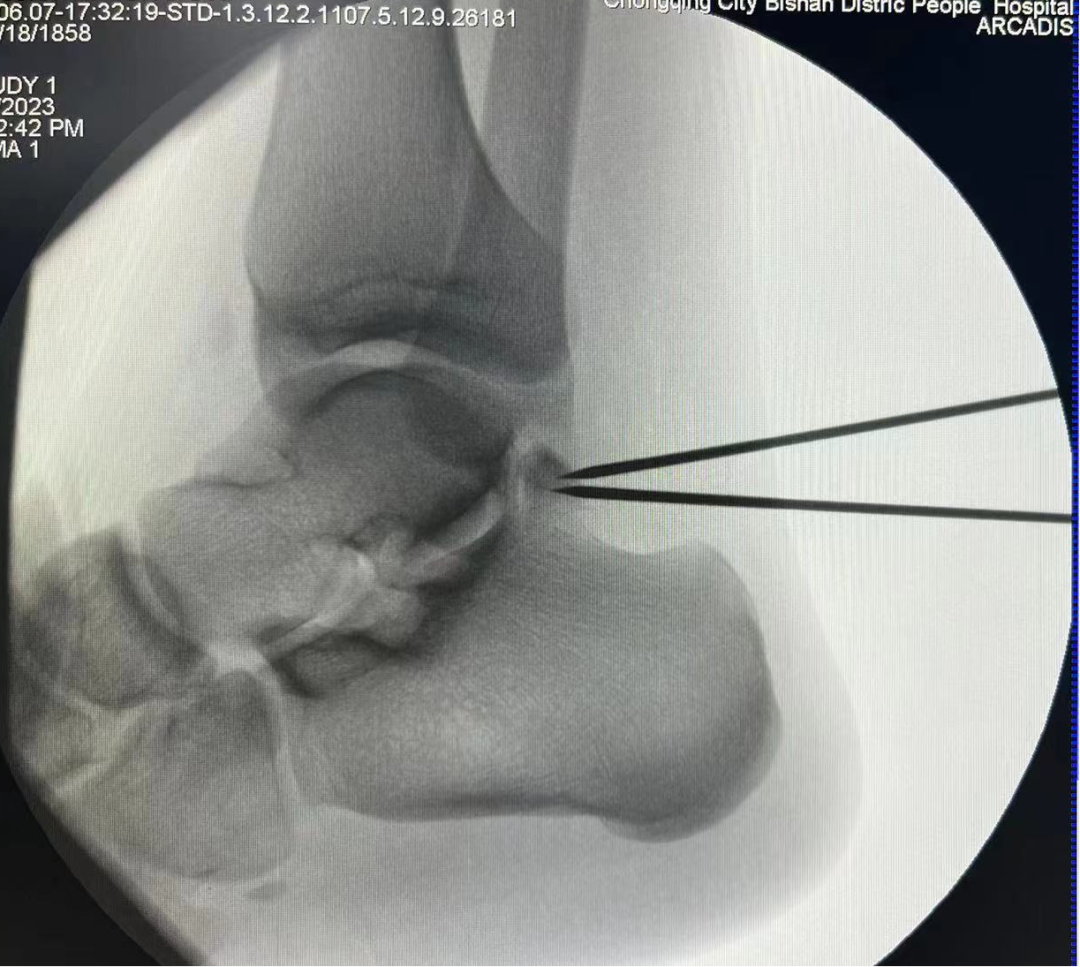

术中C臂定位病灶位置